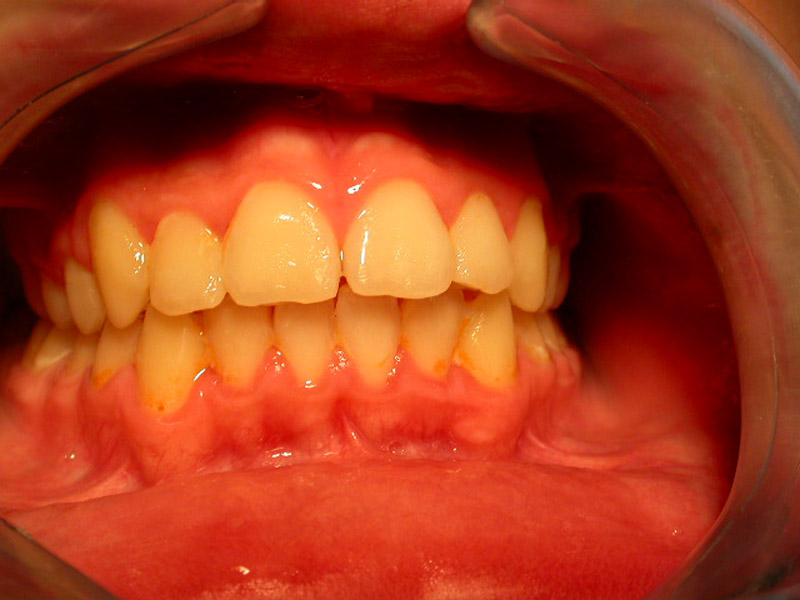

Gingivitis

Gingivitis is caused to the bacterial dental plaque. The main problems related to gingivitis are bleeding from the gums (during tooth brushing), halitosis and swelling of the gums.

Except for the bad oral hygiene, gingivitis is related to hormonal changes during puberty or pregnancy, or the presence of orthodontic mechanisms in the mouth that make difficult to maintain good oral hygiene.